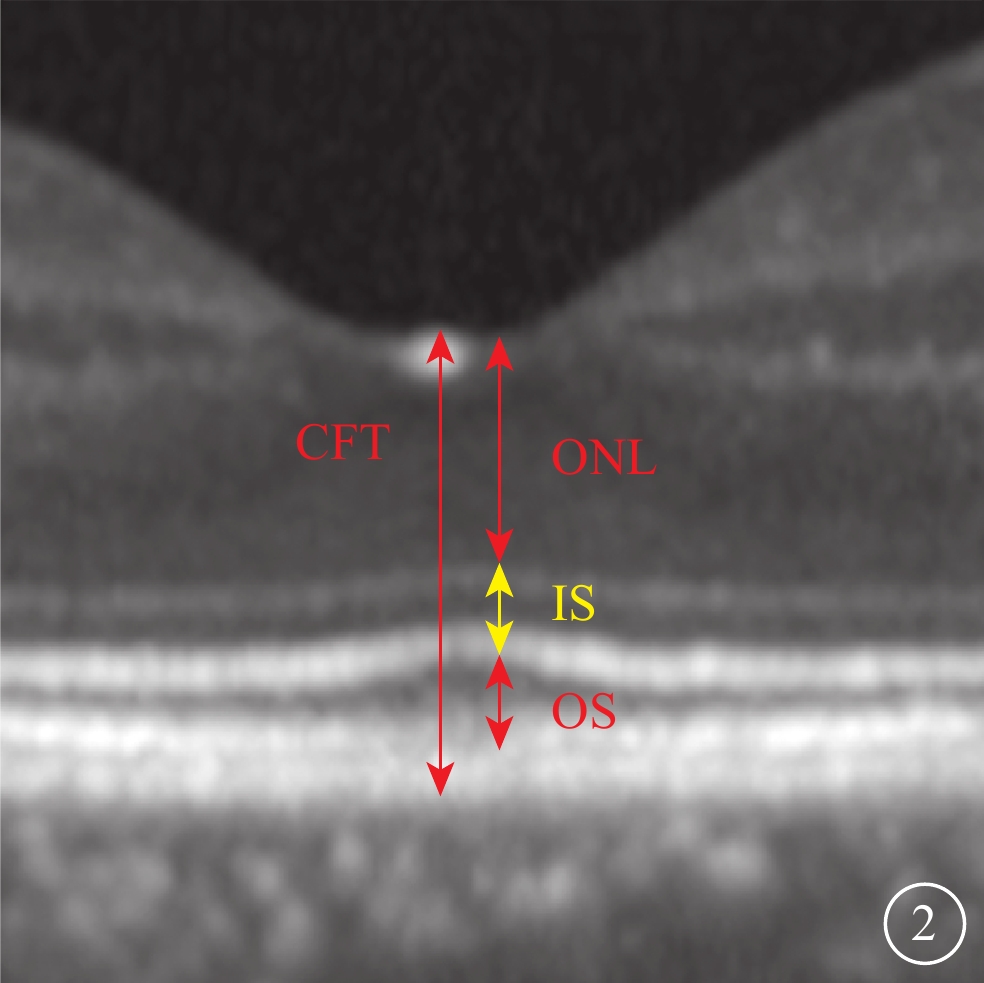

采用法國光太Supra Scan 577 nm多點掃描距陣激光器的持續激光模式或微脈沖激光模式。CLT治療參數:曝光時間0.05 s,光斑直徑100 μm,能量50~60 mW,光斑數量18~27個。SLT治療采用Supra Scan 577 nm微脈沖激光模式。治療參數:曝光時間2.00 ms,占空比5%,光斑直徑160 μm,能量250~400 mW。兩種治療方式的治療區域均為滲漏點周圍區域。所有治療均由同一位經驗豐富的眼底病醫生完成。由一位有經驗的特檢科醫生采用SD-OCT儀(Heidelberg Eye Version 1.8.6.0頻域OCT系統),對中心凹進行9 mm橫、豎單線掃描,以及黃斑區6 mm×6 mm范圍內25個斷面橫掃描,并采用隨訪模式保證每次隨訪掃描時的位置不變。選取經過中心凹的水平方向掃描圖像用于視網膜微結構評估。定性評估包括中心凹下EZ、嵌合體帶(IZ)的完整性和RPE平滑性。EZ、IZ完整性分為完整或不完整,不完整定義為OCT下相應層次連續性中斷(圖1A,1B)。RPE平滑性分為平滑或粗糙,粗糙定義為RPE局部隆起(圖1C)、RPE脫離(PED)(圖1D)、RPE增厚。定量評估包括中心凹視網膜厚度(CFT)和外核層(ONL)、內節(IS)、OS厚度。CFT定義為內界膜(ILM)內界至RPE外界的垂直距離。ONL定義為ILM外界至外界膜(ELM)內界的垂直距離。IS定義為ELM至EZ外界的垂直距離。OS定義EZ外界至RPE內界的垂直距離(圖2)。上述所有評價指標均由兩位眼科醫生分別盲態下單獨讀取,其中定量指標取兩者平均值納入統計,定性指標若存在爭議進一步討論并確定最終結果。

圖2

視網膜各層厚度測量示意圖

圖2

視網膜各層厚度測量示意圖

采用法國光太Supra Scan 577 nm多點掃描距陣激光器的持續激光模式或微脈沖激光模式。CLT治療參數:曝光時間0.05 s,光斑直徑100 μm,能量50~60 mW,光斑數量18~27個。SLT治療采用Supra Scan 577 nm微脈沖激光模式。治療參數:曝光時間2.00 ms,占空比5%,光斑直徑160 μm,能量250~400 mW。兩種治療方式的治療區域均為滲漏點周圍區域。所有治療均由同一位經驗豐富的眼底病醫生完成。由一位有經驗的特檢科醫生采用SD-OCT儀(Heidelberg Eye Version 1.8.6.0頻域OCT系統),對中心凹進行9 mm橫、豎單線掃描,以及黃斑區6 mm×6 mm范圍內25個斷面橫掃描,并采用隨訪模式保證每次隨訪掃描時的位置不變。選取經過中心凹的水平方向掃描圖像用于視網膜微結構評估。定性評估包括中心凹下EZ、嵌合體帶(IZ)的完整性和RPE平滑性。EZ、IZ完整性分為完整或不完整,不完整定義為OCT下相應層次連續性中斷(圖1A,1B)。RPE平滑性分為平滑或粗糙,粗糙定義為RPE局部隆起(圖1C)、RPE脫離(PED)(圖1D)、RPE增厚。定量評估包括中心凹視網膜厚度(CFT)和外核層(ONL)、內節(IS)、OS厚度。CFT定義為內界膜(ILM)內界至RPE外界的垂直距離。ONL定義為ILM外界至外界膜(ELM)內界的垂直距離。IS定義為ELM至EZ外界的垂直距離。OS定義EZ外界至RPE內界的垂直距離(圖2)。上述所有評價指標均由兩位眼科醫生分別盲態下單獨讀取,其中定量指標取兩者平均值納入統計,定性指標若存在爭議進一步討論并確定最終結果。

圖2

視網膜各層厚度測量示意圖

圖2

視網膜各層厚度測量示意圖